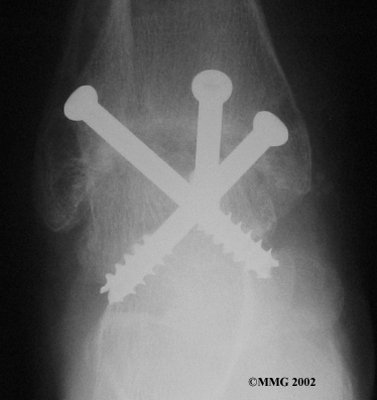

It is important when the surfaces are removed that the angles of the cut surfaces are correct. When the tibia is brought against the talus, the foot should be at a right angle to the lower leg. Once the cuts are made the bones must be held in place while they fuse. This can be done using large metal screws and metal plates if necessary. The screws are usually under the skin and are not removed unless they begin to rub and cause pain.

Inserting the screws

Using the arthroscope to watch, other instruments are inserted into the ankle joint to remove the cartilage surface. The cartilage surface is removed using a small rotary cutting tool. Once the surfaces are prepared, screws are placed through small incisions in the skin to hold the bones together as they heal, or fuse. This procedure is not significantly different from the open procedure except that the incisions are smaller.

After ankle fusion, the physical therapists at FYZICAL Doylestown can help you learn to walk smoothly and without a limp. Although time needed for recovery varies among patients, an ankle brace will typically replace your cast after eight to 12 weeks. Your surgeon will take X-rays frequently to see if the bones are fusing together. You will probably need to use crutches during the time you wear the cast. As the fusion grows stronger, you will begin to put more weight on your foot when walking.